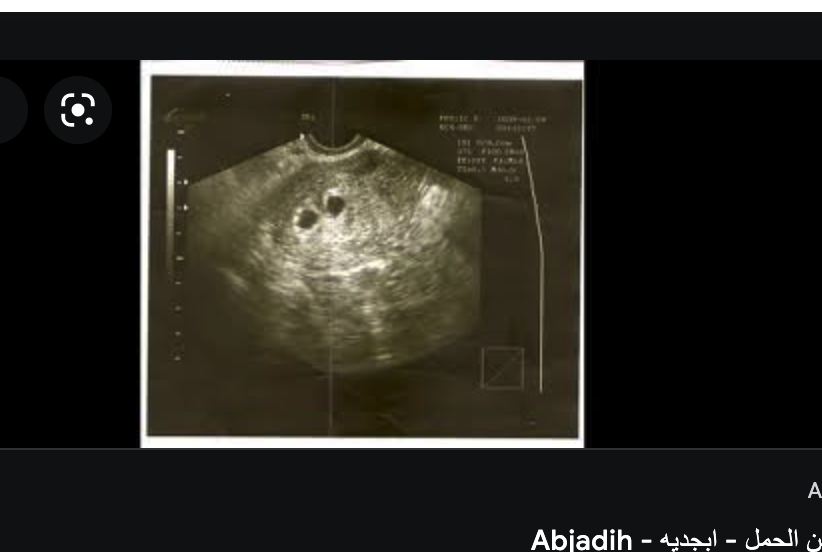

السلام عليكم ورحمة الله بنات شوفوا سوناري خمس اسابيع ويومين تؤام او ايش النقطتين هذي؟

والله ياقلبي ماني عارفه لكن الله يرزقك بما تتمنين يارب♥️♥️